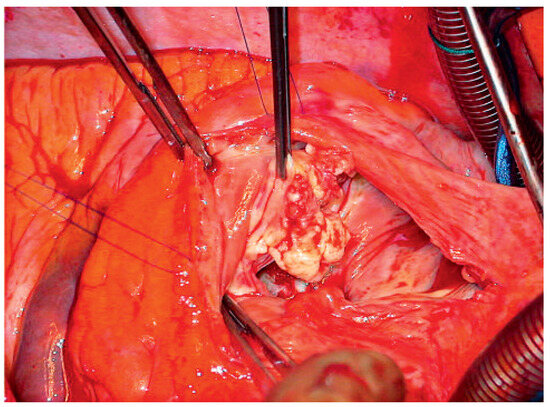

A Case of Infective Endocarditis Caused by Bartonella Quintana: Prolonged Mild Symptoms and a Sudden Life-Threatening Complication

by Florian S. Schoenhoff, Friedrich S. Eckstein, Stefan Zimmerli and Thierry P. Carrel

Cardiovasc. Med. 2009, 12(11), 315; https://doi.org/10.4414/cvm.2009.01455 - 13 Nov 2009

The morbidity and mortality associated with infective endocarditis can be significantly reduced by early diagnosis and initiation of effective therapy. Due to the often nonspecific prosaic symptoms associated with infective endocarditis, patients are likely to seek initial medical care from their primary care [...] Read more.

The morbidity and mortality associated with infective endocarditis can be significantly reduced by early diagnosis and initiation of effective therapy. Due to the often nonspecific prosaic symptoms associated with infective endocarditis, patients are likely to seek initial medical care from their primary care physicians. The authors present the history of a patient suffering from indolent prolonged illness with moderate fever who developed painless macrohematuria and triple valve endocarditis with Bartonella quintana. This pathogen is a gram-negative bacterium responsible for the epidemic louse-borne trench-fever seen in Europe during World War I and particularly seen as an infectious agent in HIV patients. Full article

Show Figures

Figure 1